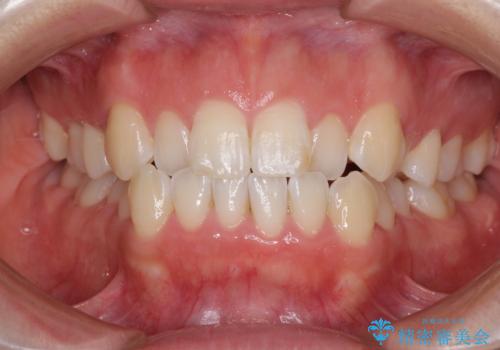

- 口元の突出感と口の閉じにくさ、前歯のデコボコを気にして来院された患者様です。

上下左右第一小臼歯4本を抜歯し、ワイヤー装置にて口元を引っ込めるよう矯正治療を行うこととしました。

骨格的に下顎骨が前方位にあるため、口元の突出感改善には限界があると思われましたが、唇の閉じにくさが改善するほど引っ込めることができました。